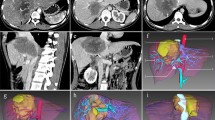

An aberrant artery (AA) can be frequently observed coursing through the fissure for the ligamentum venosum (FLV) on axial contrast-enhanced computed tomography (CT) or magnetic resonance imaging (MRI) scans (Fig. 1-A). We termed this manifestation the “vessel through strait” sign (VTSS), as the AA highly resembles a “vessel” which is sailing though a “strait” composed of segment I (S1) and segment II (S2) of the liver (Fig. 1-B). VTSS is estimated to be observed in approximately 15–20% of the general population according to our experience, however, despite being sparsely described as the variant left hepatic artery (LHA)1,2, or variant common hepatic artery (CHA)3 or accessory left gastric artery (LGA)4, current knowledge about VTSS and the AAs composing VTSS is very limit, fundamental data including its incidence, anatomical composition and clinical significance are lacking. To address this issue, in the present study, we respectively analyzed the hepatic arteriographic and CT/MRI data in 2,275 patients receiving transcatheter arterial chemoembolization (TACE) with a particular focusing on the VTSS. A very interesting result of our analysis was that nearly 90% of the patients exhibiting VTSS were proved to have left hepatic artery variation (LHAV). The strong association between VTSS and LHAV naturally drove us to propose and validate the hypothesis that VTSS is a signature radiographic sign of LHAV that could be used for its diagnosis.

(A) A typical VTSS (white dashed square) formed by a replaced LHA entering liver through FLV was seen in the arterial phase of a contrast-enhanced CT scan. (B) A schematic diagram of VTSS. The vessel represents the aberrant artery, which is sailing though a “strait” composed of S1 and S2 of the liver (C) The patient was confirmed to have a replaced LHA arising from LGA (Michel’s type II HAV) by DSHA. The corresponding part of the replaced LHA forming VTSS was highlighted by the white dashed rectangle. LHA, left hepatic artery; LGA, left gastric artery; RHA, right hepatic artery; S, segment of the liver; T, thoracic vertebrae.

The incidence of VTSS and the anatomical compositions of the AAs seen in VTSS

The presence of VTSS was screened in a training cohort of 2,275 patients and was identified in 357 (15.7%) of them. Representative images of VTSS are shown in Fig. 1 and the supplementary figures. In each patient with VTSS, the anatomical property of the observed AA was further analysed according to the hepatic arteriography data. As shown in Table 1, the anatomical composition of the VTSS-associated AA was as follows: replaced LHA (n = 246, 68.9%, Fig. 1-C), accessory LHA (n = 64, 17.9%, supplementary fig. 1), common hepatic artery (CHA) (n = 8, 2.2%, supplementary fig. 2), accessory LGA (n = 26, 7.3%, supplementary fig. 3), left inferior phrenic artery (LIPA) (n = 3, 0.8%, supplementary fig. 4) and the common trunk of accessory LGA and LIPA (n = 10, 2.9%, supplementary fig. 5). Thus, in total, 89.1% (318/357) of the patients with VTSS do indeed have LHAV. We further demonstrated the prevalence of VTSS in all of the 2,275 patients according to their Michel’s classification results. The global profile of HAV in the 2,275 patients and the incidence of VTSS of each Michel’s classification type are shown in Table 2. Overall, LHAV was detected in 318 (14.1%) patients and VTSS was observed in 312 (98.1%) of them.